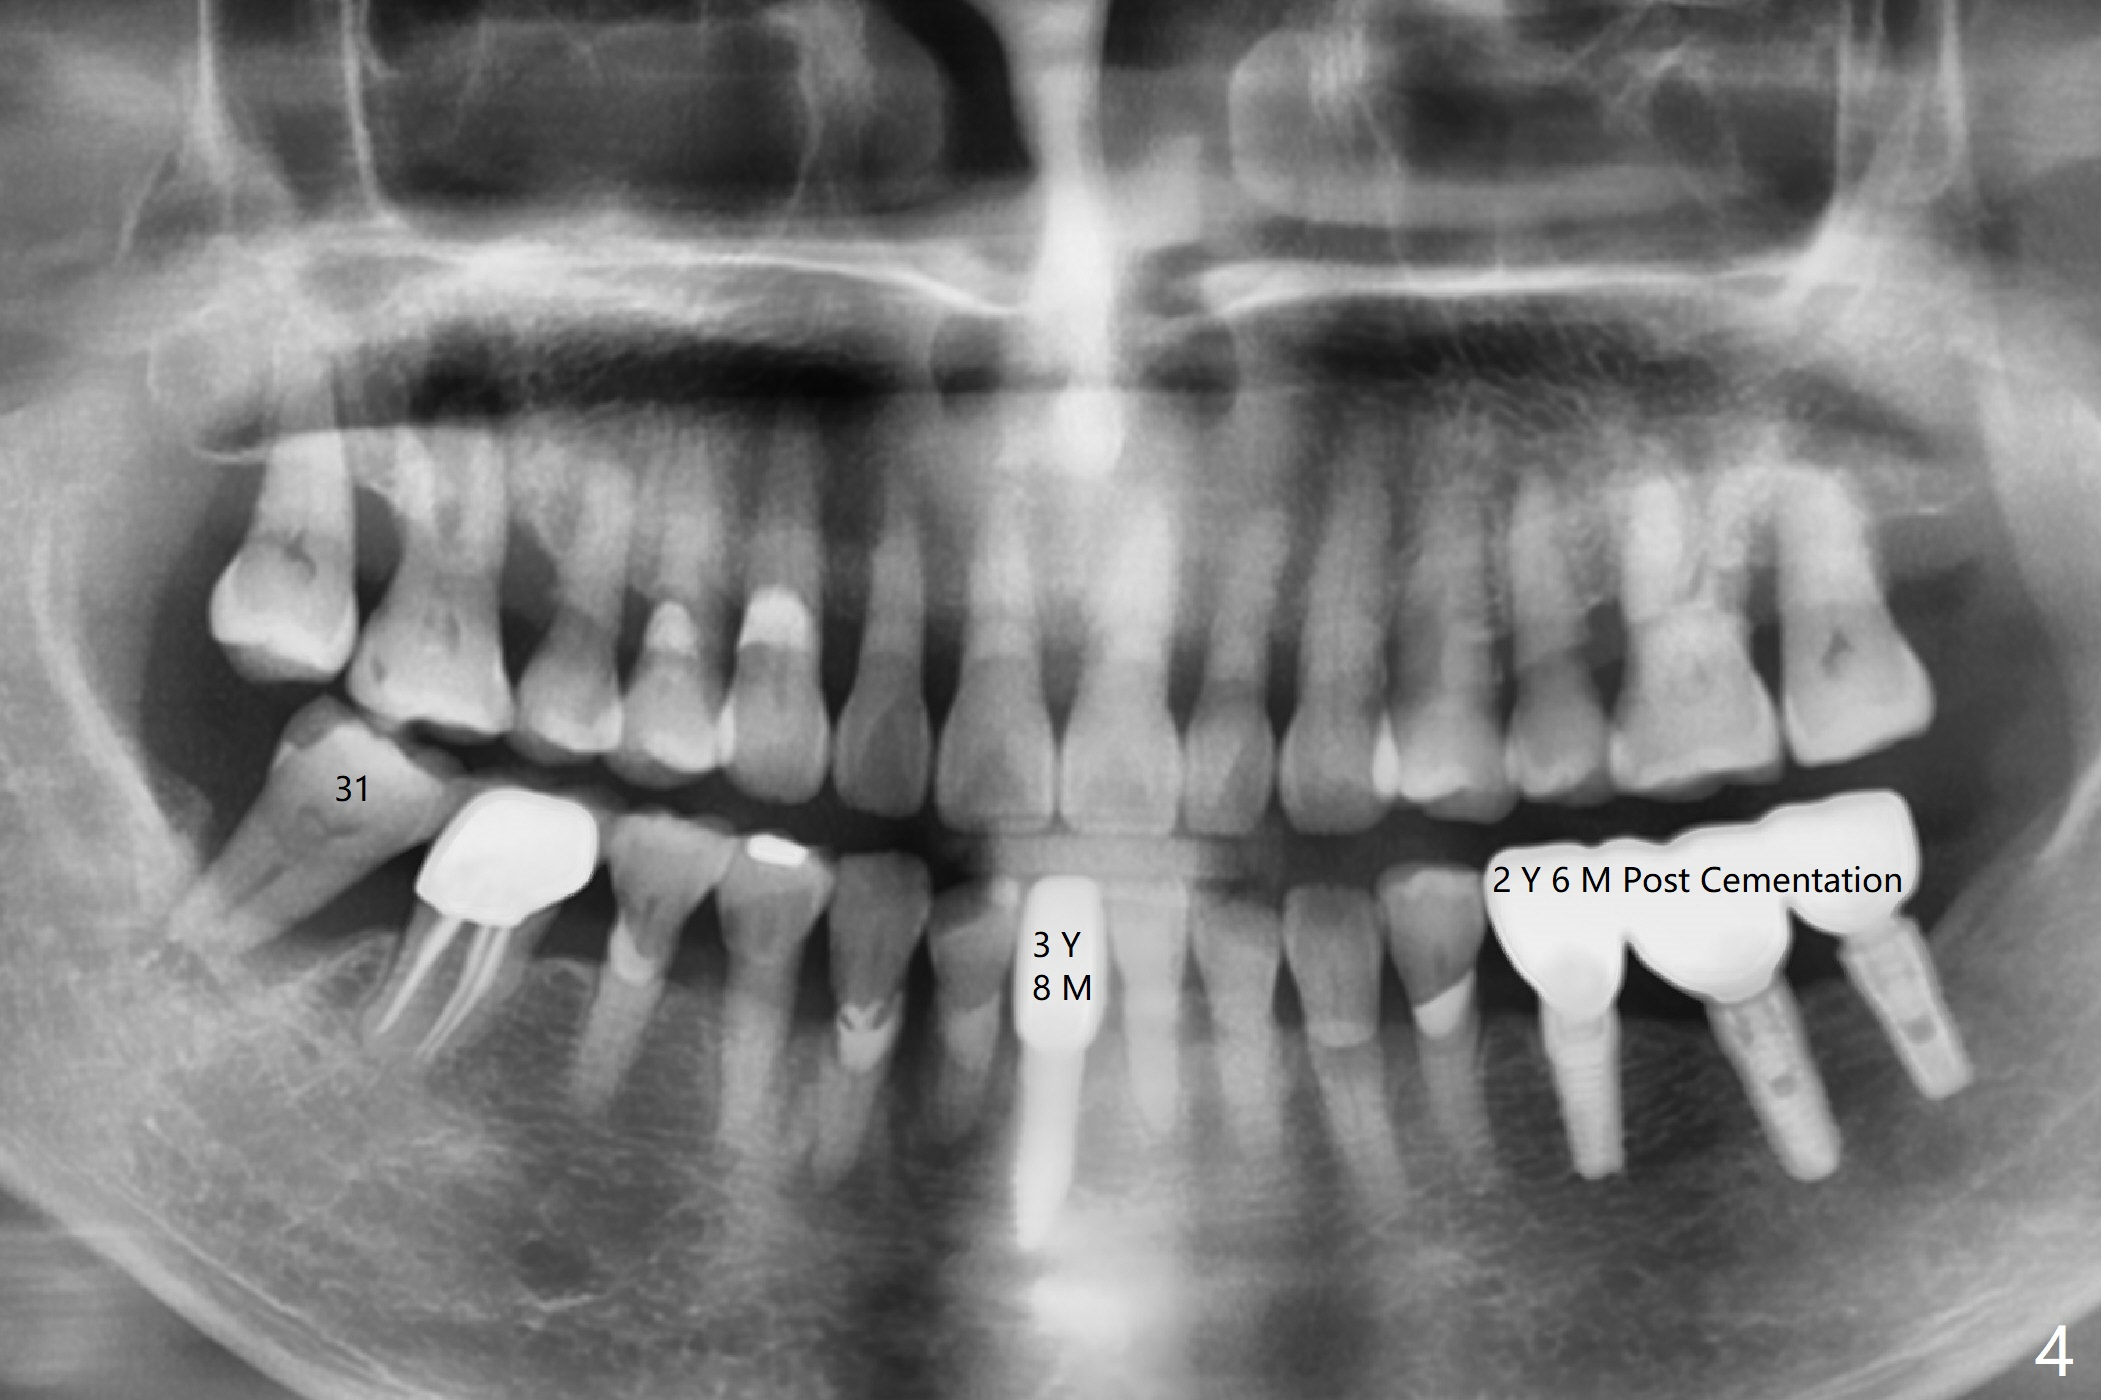

A 79-year-old woman returns to clinic suddenly, requesting extraction of the tooth #31 with mobility III (3 years 8 months post cementation for #25; 2 years 6 months post cementation for #18-20; Fig.4). An immediate implant is planned (Fig.1). After extraction, the large socket has relatively small opening, seemingly easy to keep bone graft in place. The immediate implant with 2-3 mm native bone may not have primary stability, most likely losing its ability to hold bone graft. Therefore socket preservation is conducted at #31. In contrast there is enough bone for an immediate implant at #15 (Fig.2) with palatal root fracture (Fig.3 (palatal view)).